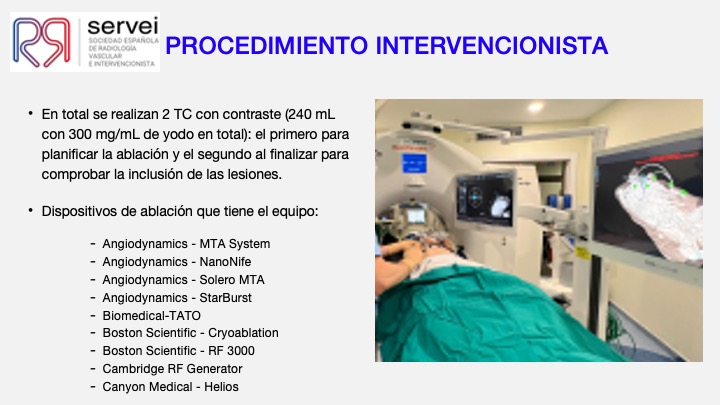

- Ablacion estereoataxia lesiones hepaticas 01

- Ablacion estereoataxia lesiones hepaticas 02

- Ablacion estereoataxia lesiones hepaticas 03

- Ablacion estereoataxia lesiones hepaticas 04

- Ablacion estereoataxia lesiones hepaticas 05

- Ablacion estereoataxia lesiones hepaticas 06

- Ablacion estereoataxia lesiones hepaticas 07

- Ablacion estereoataxia lesiones hepaticas 08

- Ablacion estereoataxia lesiones hepaticas 09

- Ablacion estereoataxia lesiones hepaticas 10

- Ablacion estereoataxia lesiones hepaticas 11

- Ablacion estereoataxia lesiones hepaticas 12

- Ablacion estereoataxia lesiones hepaticas 13

- Ablacion estereoataxia lesiones hepaticas 14